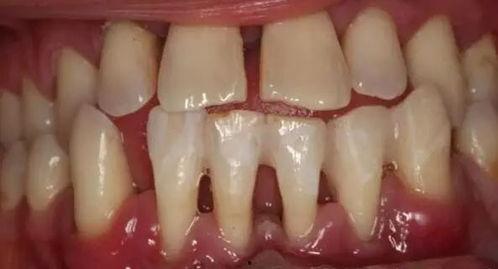

1. 清洁口腔:在进行牙周夹板固定之前,医生会先帮你彻底清洁口腔,确保口腔卫生。

6. 保持口腔卫生:牙周夹板固定期间,保持口腔卫生至关重要,否则容易引发口腔问题。

2. 清洁口腔:医生使用专业工具清洁患者口腔,确保口腔卫生。

7. 保持口腔卫生:医生提醒患者保持口腔卫生,避免口腔问题。

3. 保持口腔卫生:保持口腔卫生是牙周夹板固定期间的关键,否则容易引发口腔问题。